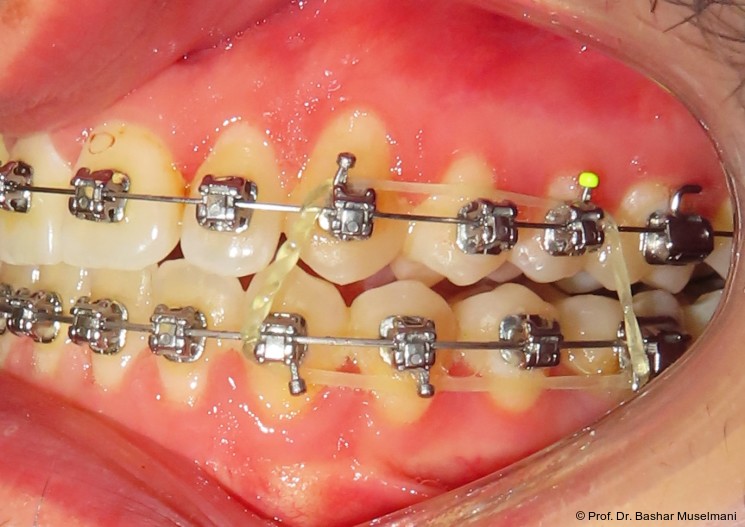

Zur sagittalen Korrektur wurden intermaxilläre Klasse III-Gummizüge eingesetzt.

Zu Beginn der Nivellierungsphase wurden in beiden Kiefern 0.013" CuNiTi-Bögen eingesetzt (Abb. 4a–e).

Diese Sequenz ermöglichte eine schrittweise Ausformung der Zahnbögen, eine kontrollierte Torque-Expression sowie eine präzise Feineinstellung in der Abschlussphase (Abb. 5a–e).